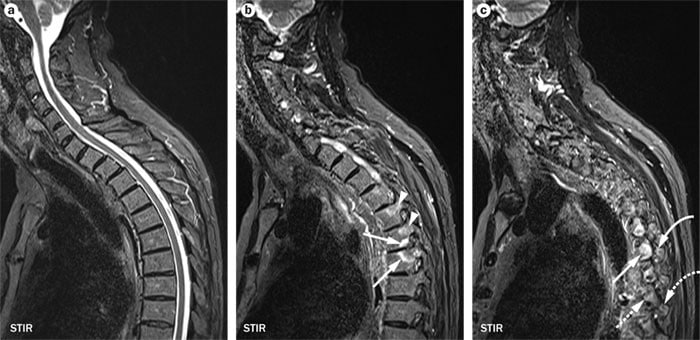

Российские специалисты готовы представить первый в мире препарат против болезни Бехтерева Сенипрутуг Он точечно воздействует на аутоиммунные клетки без подавления иммунитета Препарат вводят раз в полгода год что снижает риск привыкания Разработка заняла почти два десятилетия Болезнь Бехтерева поражает суставы позвоночника и таза вызывая боли и ограничение подвижности naukaitochka